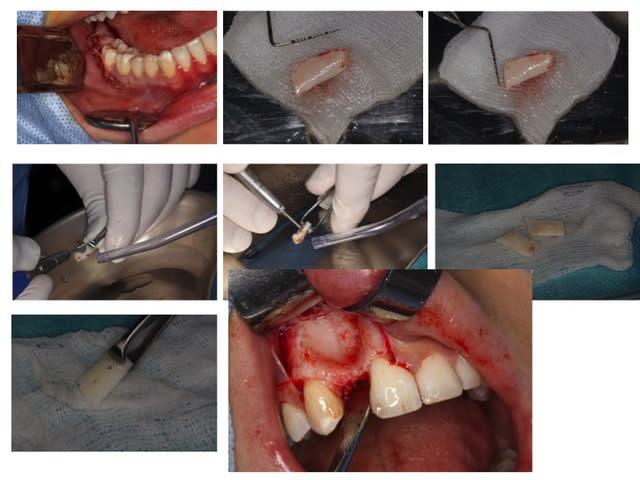

Greffe 2D:

Greffon mince en vestibulaire qui coulisse sur les deux vis, on écarte du SR ( photo avec syndesmotome faucille) on glisse dessous les fragments copeaux d'os et on ressert un peu à la fin

Donc le greffon cortical sert de membrane pour protéger le lit de copeaux

Prélèvement rétromolaire/ramique

Séparation du greffon en deux et mise en forme

Préparation des trous de vis en diam 1,5 pour vis de 1,3 et cuvette pour les têtes de vis

Pince de barth pour maintenir le greffon et forage dans les trous au forêt de 1mm et mise en place des vis. Le greffon est libre, pour pouvoir régler l'épaisseur souhaitée.

Broyage du reste du prélèvement

Le greffon est soulevé pour glisser dessous le broyât osseux